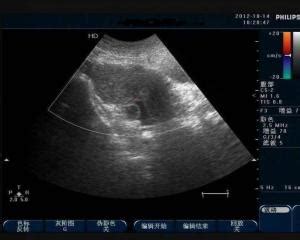

如果排除了生理性盆腔积液的可能性,反复多次检查出的盆腔积液量多,且有白带过多、下腹痛、腰痛、发烧等症状,那么则考虑是盆腔炎症、卵巢肿瘤或者肠道肿瘤引起的盆腔积液反反复复。

这种情况建议及时到正规医院就,查明病因,及时治疗疾病。